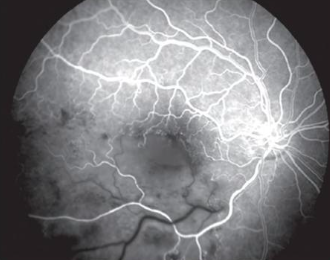

• A branch retinal vein occlusion resulting in areas of non-filling of the retinal vessels.

A filling defect causes hypofluorescence due to reduced perfusion - meaning less fluorescein is reaching the vasculature. If there is a complete absence of perfusion, the hypofluorescence will persist throughout the whole angiogram. If there is only partially reduced perfusion, there will be delayed filling.